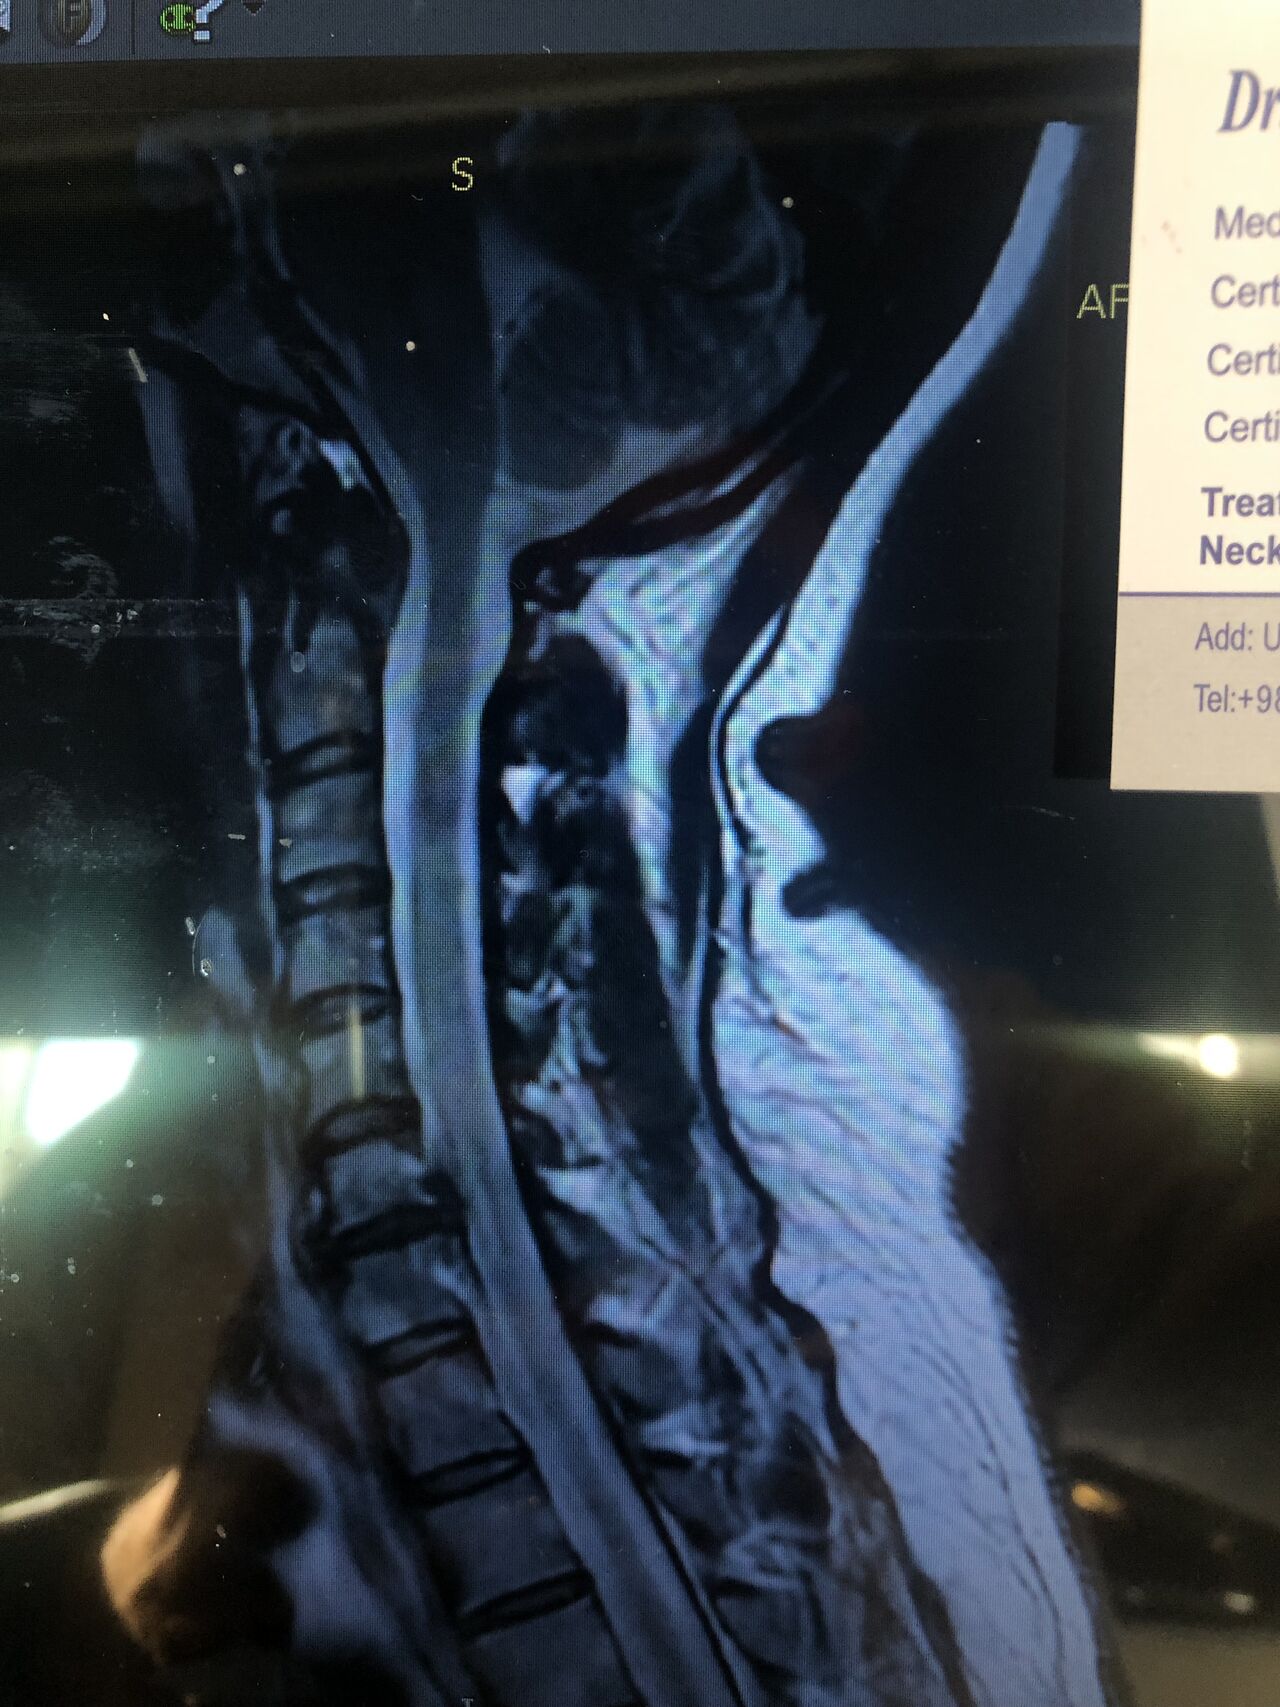

A 56-year-old man presented with chronic low back pain and mild neck stiffness. Lumbar MRI confirmed disc degeneration. In cervical MRI C5-6 Cervical extrusion with cervical cord compression is seen

And neurological exams were normal for cervical spine

therefore according to the cervical mri no cervical treatment was rendered to his neck

Insurance initially denies paying for MRI but patients can pay themselves if they want to get neck adjustment

.cervical adjusting was not rendered and patient was referred to the neurosurgeon

Although the patient was asymptomatic from a cervical standpoint, MRI findings demonstrated cervical cord severe compression and possible mild edema and early myelomalacia. Based on these findings, I believe that cervical decompression surgery should be considered.

While some neurologists and chiropractors may defer intervention in the absence of overt clinical symptoms, in this case, early surgical decompression appears justified. Waiting for neurological deficits—such as gait imbalance, coordination difficulties, or gastrointestinal/genitourinary dysfunction—may result in irreversible spinal cord injury, as these deficits often persist even after surgical decompression.

Considering the patient’s age and progressive degenerative changes, including degenerative disc disease (DDD) and degenerative joint disease (DJD), delaying surgery could further increase the risks associated with operative morbidity and mortality. Keep in mind all kind of manipulation on his neck is absolutely contraindicated